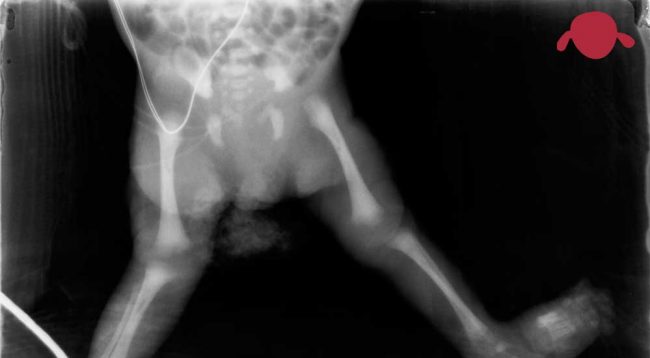

Hemos organizado un curso de Traumatología y Ortopedia Infantil práctico y directo. Con imágenes para guiar tu día a día en la consulta de pediatría. Nuestra experiencia para que salgas de aquí con ideas claras, sepas lo que sí puedes hacer en un ambulatorio y lo que nos puedes remitir a los traumatólogos infantiles…